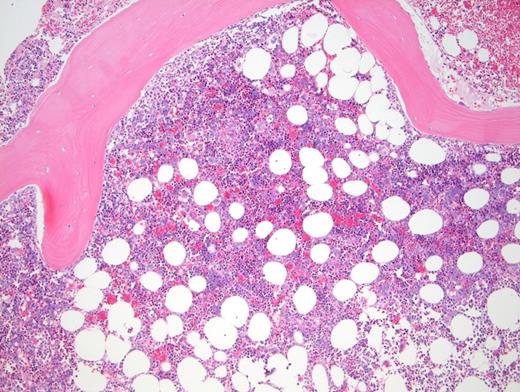

Peripheral blood showed abnormal red cell findings (Figure 1) with erythroblastosis (not shown). Aspirate showed trilineage hematopoiesis with erythroid predominance (Figure 2). Core biopsy showed hypercellular marrow (Figures 3 and 4) with focal areas of marrow damage (Figure 5). Hemoglobin high-performance liquid chromatography (HPLC) was performed (Figure 6).

The peripheral blood showed numerous target cells, burr cells, and microcytes, as well as partially sickled cells and blister-like cells. Core biopsy shows erythroid hyperplasia with large clusters of sickled cells (present in macrophages by CD68 stain; not shown).

The focal areas of bone marrow necrosis are the consequence of ischemic marrow damage caused by vascular obstruction by sickle cells. In a patient with sickle cell variant, multiorgan failure with altered mental status and focal bone marrow necrosis, the findings raise concern for bone marrow necrosis/fat embolism syndrome (BMN/FES).3 BMN/FES is more common in non– hemoglobin SS SCD variants such as hemoglobin SC.4 Brain MRI can show “starfield” on diffusion-weighted MRI in patients with severe neurologic impairment due to emboli.5,6 This patient did not undergo MRI after her decompensation.